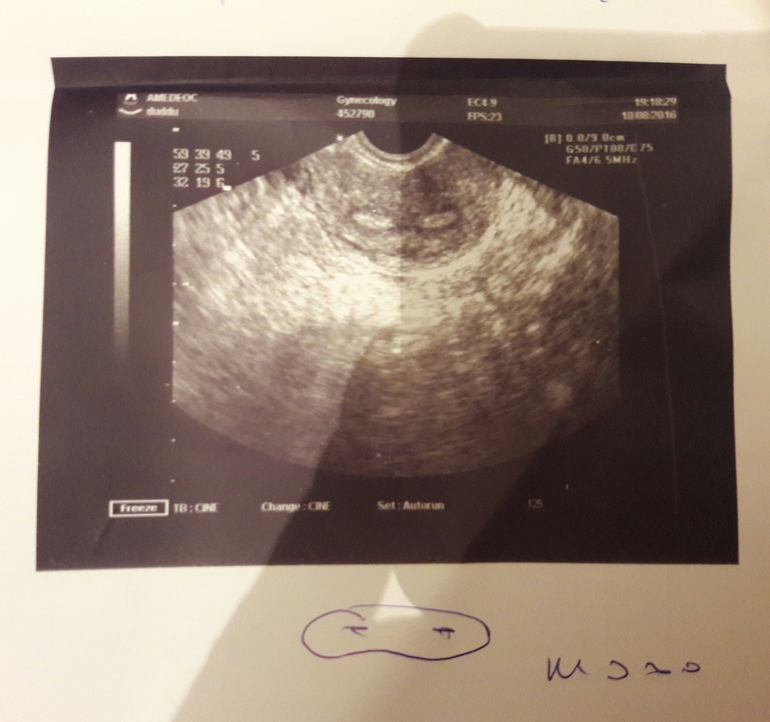

Была на узи на 21 дц.Прикрепили мне вот такое фото,что-то написали.Сразу не посмотрела,а теперь интересно-это вообще что?

Хр. Эндометрит,седловидная матка и что-то еще,не могу разобрать.Добавлю фото узи в пост для полноты картины

Это же двурогая матка ) узи забавное )))))

Седловидная,я дополнила пост фото узи

Вообще очень интересное фото) внузу подписано м эхо, но почему два???

Это кошачьи глазки-двурогая матка.

Двурогая матка! А внизу написано мэхо.